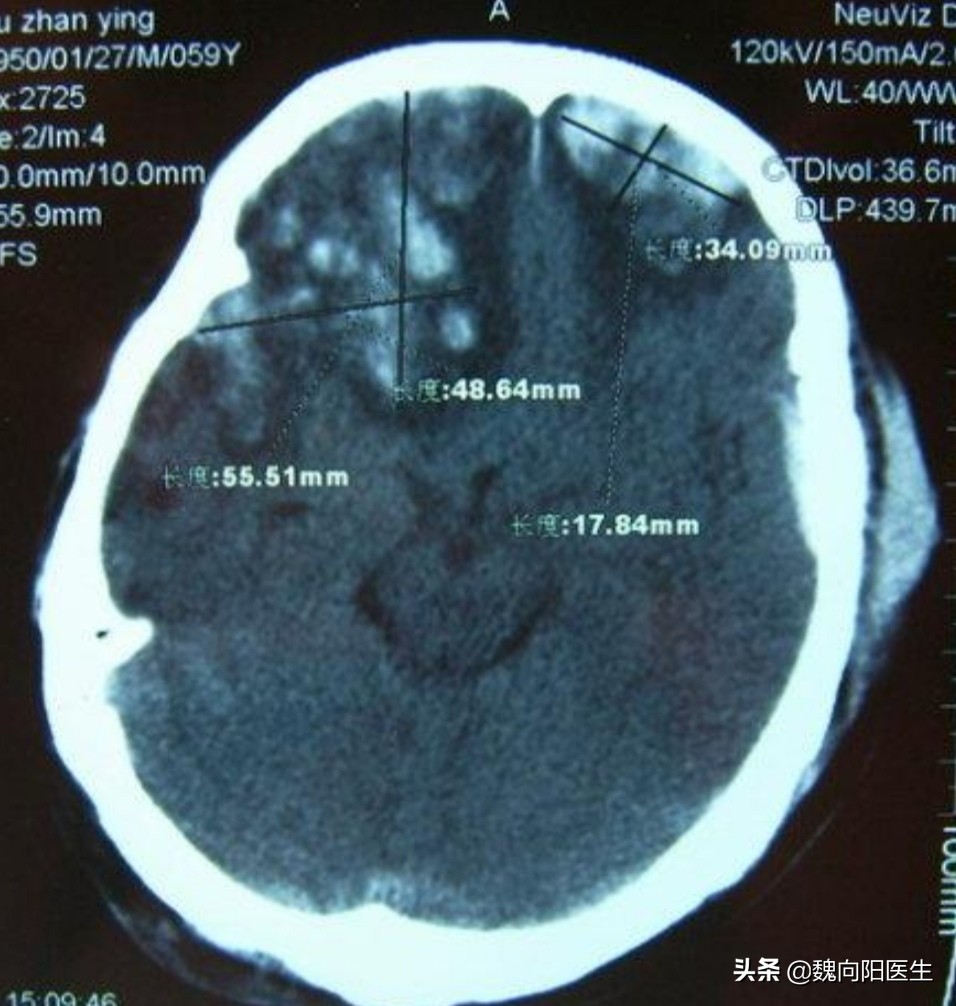

美国警察把老人用力推倒后,美国老人后退几步后摔倒在地?后脑勺着地,当时后脑勺就流血了,看摔倒的视频,应该是头部外伤不清。怀疑颅内应该也出血了。

一般撞到头部后脑勺,很多脑出血是发生在前额或前颅底部位。这叫做对冲伤。

早期出现脑额颞叶挫裂伤

由于前颅底骨头表面不光滑,且神经组织众多,在后枕部受到撞击后,导致脑组织在不光滑颅骨表面滑动,从而导致脑挫裂伤、硬膜下血肿或蛛网膜下腔出血可能。

而由于枕部骨头比较坚硬,可能并不会骨折,同时起到保护枕部脑组织的作用。